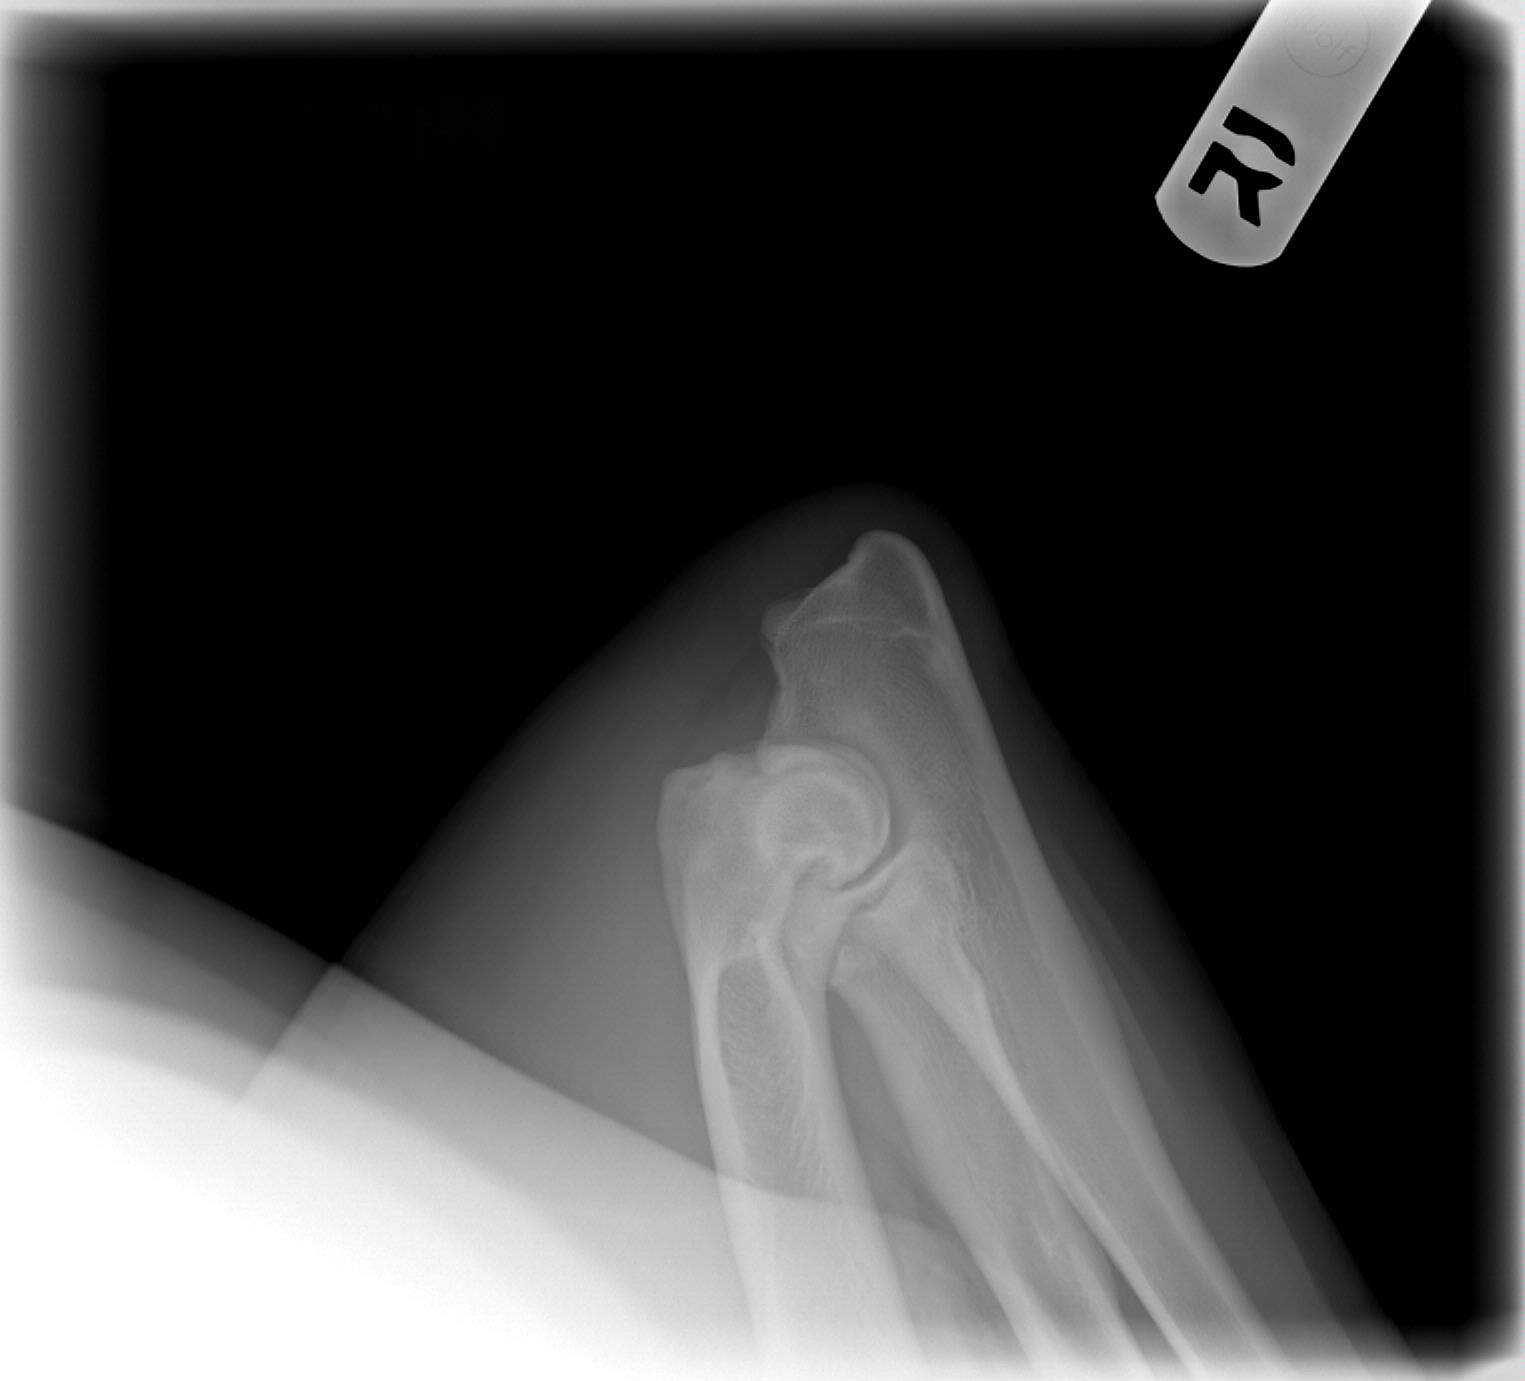

Barry's hips and elbows, taken on 1/7/08. My vet said he would be "shocked" if he did not get an Excellent but OFA gave them a Good. The third time they looked at them OFA changed one elbow from clear to Grade 1, however. We are disappointed. Both his littermates have gotten OFA Excellents, normal elbows, so that is nice. We'll try again for the perfect chocolate boy with Adam and Woody. :)